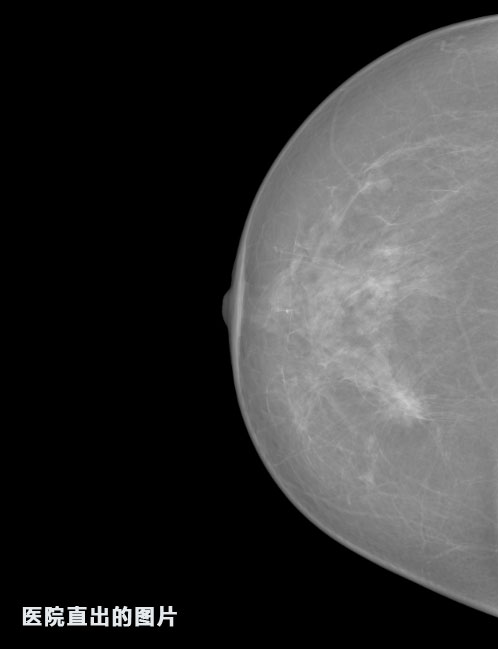

英特健康A(chǔ)I深度學(xué)習(xí)醫(yī)療圖像識(shí)別系統(tǒng)案例_乳腺